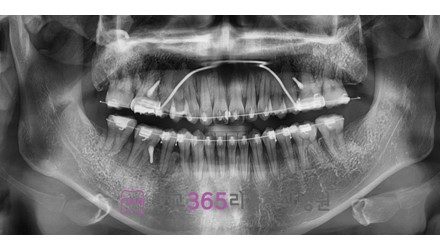

심*복 임플란트 시술 사례

전체 임플란트

2024.12.05

치료 전

2025.05.30

치료 후